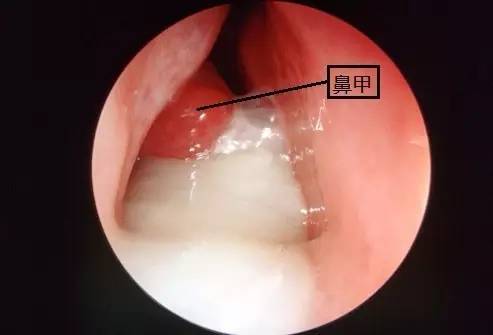

上图就是上呼吸道感染时的白色鼻涕,可以看到鼻甲是发红、肿大的,这就是炎症的表现。